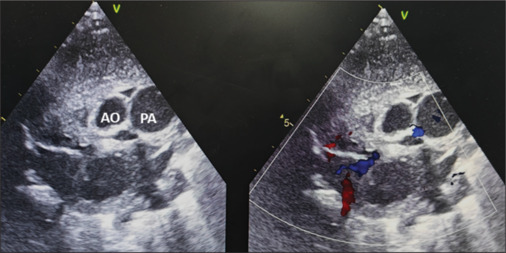

一种罕见但具有历史意义的大动脉转位(TGA)变异于1971年首次被发现。后向右的主动脉、不发达的主动脉下圆锥和发育良好的肺下圆锥是本病的特征。大血管的关系类似于正常相关的大动脉,肺动脉位于前面,主动脉位于后面。本报告描述了一例TGA变异伴室间隔缺损的患者,该患者接受了成功的动脉转换手术。尽管大动脉的位置不寻常,冠状动脉转移和肺动脉吻合是有效的。尽管已发表的文献建议在这种解剖结构中不采用LeCompte手法,但我们在该病例中采用了前后环状冠状动脉,以保护近端冠状动脉免受过度拉伸。

A rare but historically significant variant of transposition of the great arteries (TGA) was first identified in 1971. A posterior and rightward-positioned aorta, an underdeveloped subaortic conus, and a well-developed subpulmonary conus characterize this entity. The relationship of the great vessels mimics that of normally related great arteries, with the pulmonary artery positioned anteriorly and the aorta located posteriorly. This report describes a patient with such a variant of TGA, associated with a ventricular septal defect, who underwent a successful arterial switch operation. Despite the unusual positioning of the great arteries, coronary artery transfer and pulmonary artery anastomosis were effectively performed. Although published literature advises against performing LeCompte's maneuver in such anatomy, we performed the maneuver in this case with anterior and posterior looping coronaries to protect the proximal coronary arteries from excessive stretch.